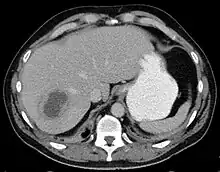

A large pyogenic liver abscess presumed to be the result of appendicitis